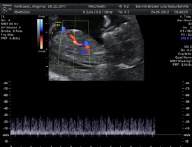

* First Trimester Screening. Messung der Nackentransparenz, Nasenbein, Combined Test (12.-14. SSW) - hier Termin vereinbaren!

d.h. pränataler Ultraschall (Messung der Nackendicke, Organscreening) einerseits, andererseits kann noch eine Untersuchung mittels 4D-Ultraschall durchgeführt werden,